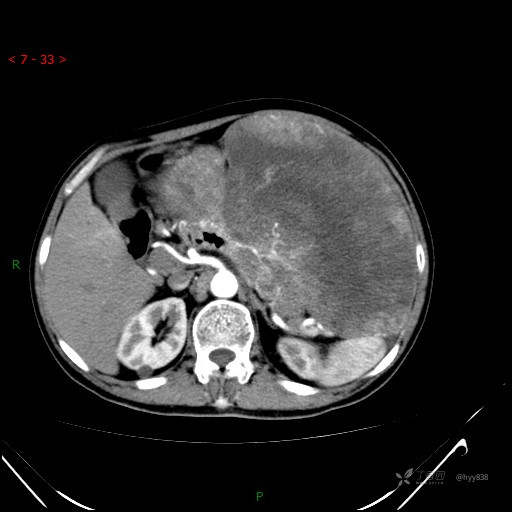

增强静脉期